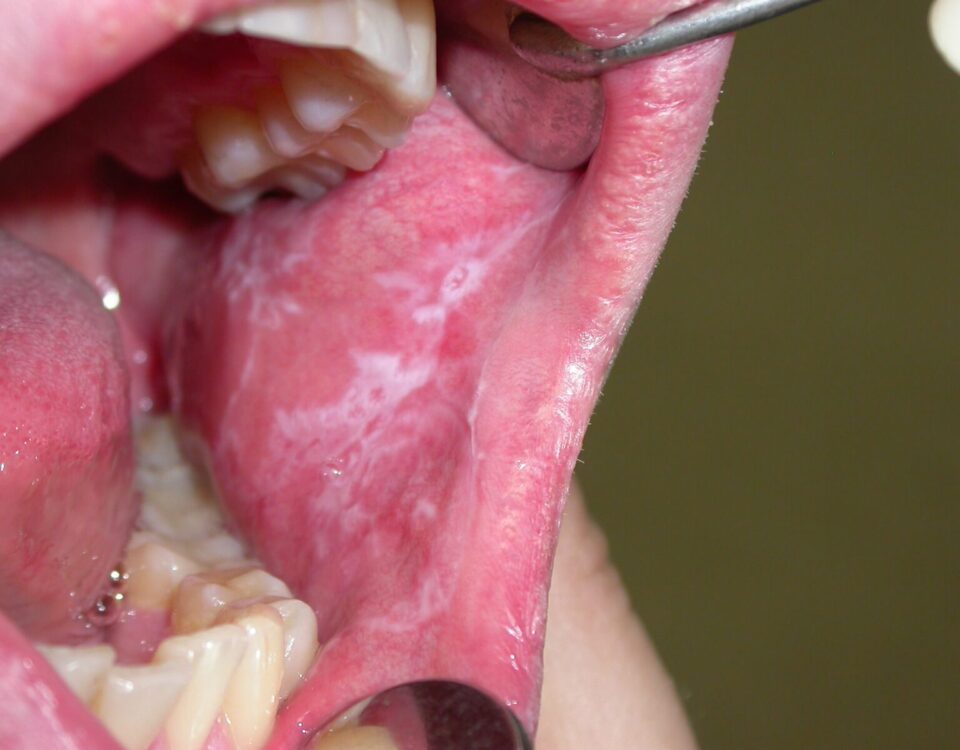

- Leukoplakia

- Lezionet Orale Prekanceroze: Njohja dhe Parandalimi i Kancerit Oral

- Kanceri Oral / Kanceri i Gojës